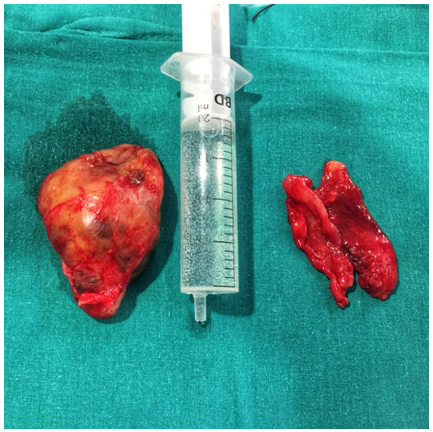

We completed the study with MR that reported an ovoid lesion of heterogeneous structure and cystic areas inside, with measurements of 37x33x69mm with well-defined borders, maintaining a fatty plane of separation with muscles (signs of non-aggressive lesion), without contrast highlights or signal intensity changes of the muscles adjacent to the lesion (Figure 1). It contacted and displaced the sciatic nerve medially, depending on one of the fascicles of the nerve. With contrast administration, the absorption was progressive, obtaining low-medium values respect to the arterial peak, being compatible with a nervous sheath tumor.

Figure 1 MR of the lower extremities without contrast, coronal cut: ovoid lesion of heterogeneous structure and dependent areas of one of the fascicles of the sciatic nerve (arrow).